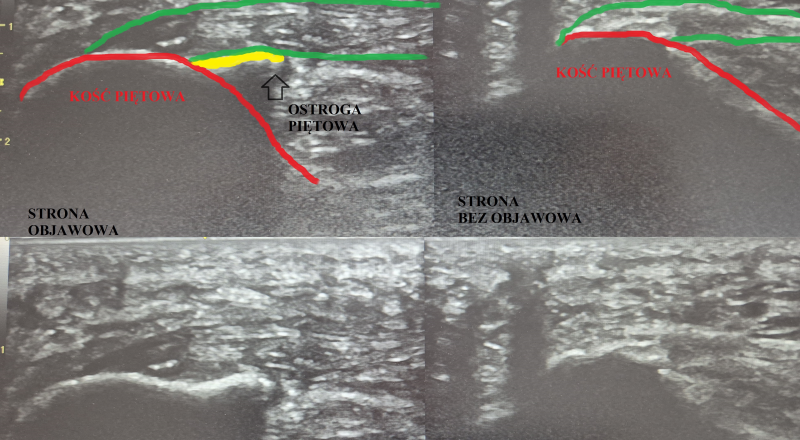

Obraz USG: Zdrowa stopa vs Zapalenie rozścięgna

W diagnostyce kluczowe jest porównanie. Na zdjęciach USG moich pacjentów wyraźnie widać różnice, które decydują o doborze terapii:

Wniosek: Jeśli Twoje rozścięgno jest pogrubione i "ciemne" w obrazie USG, oznacza to zmiany przeciążeniowe, które wymagają celowanej interwencji, a nie tylko odpoczynku.